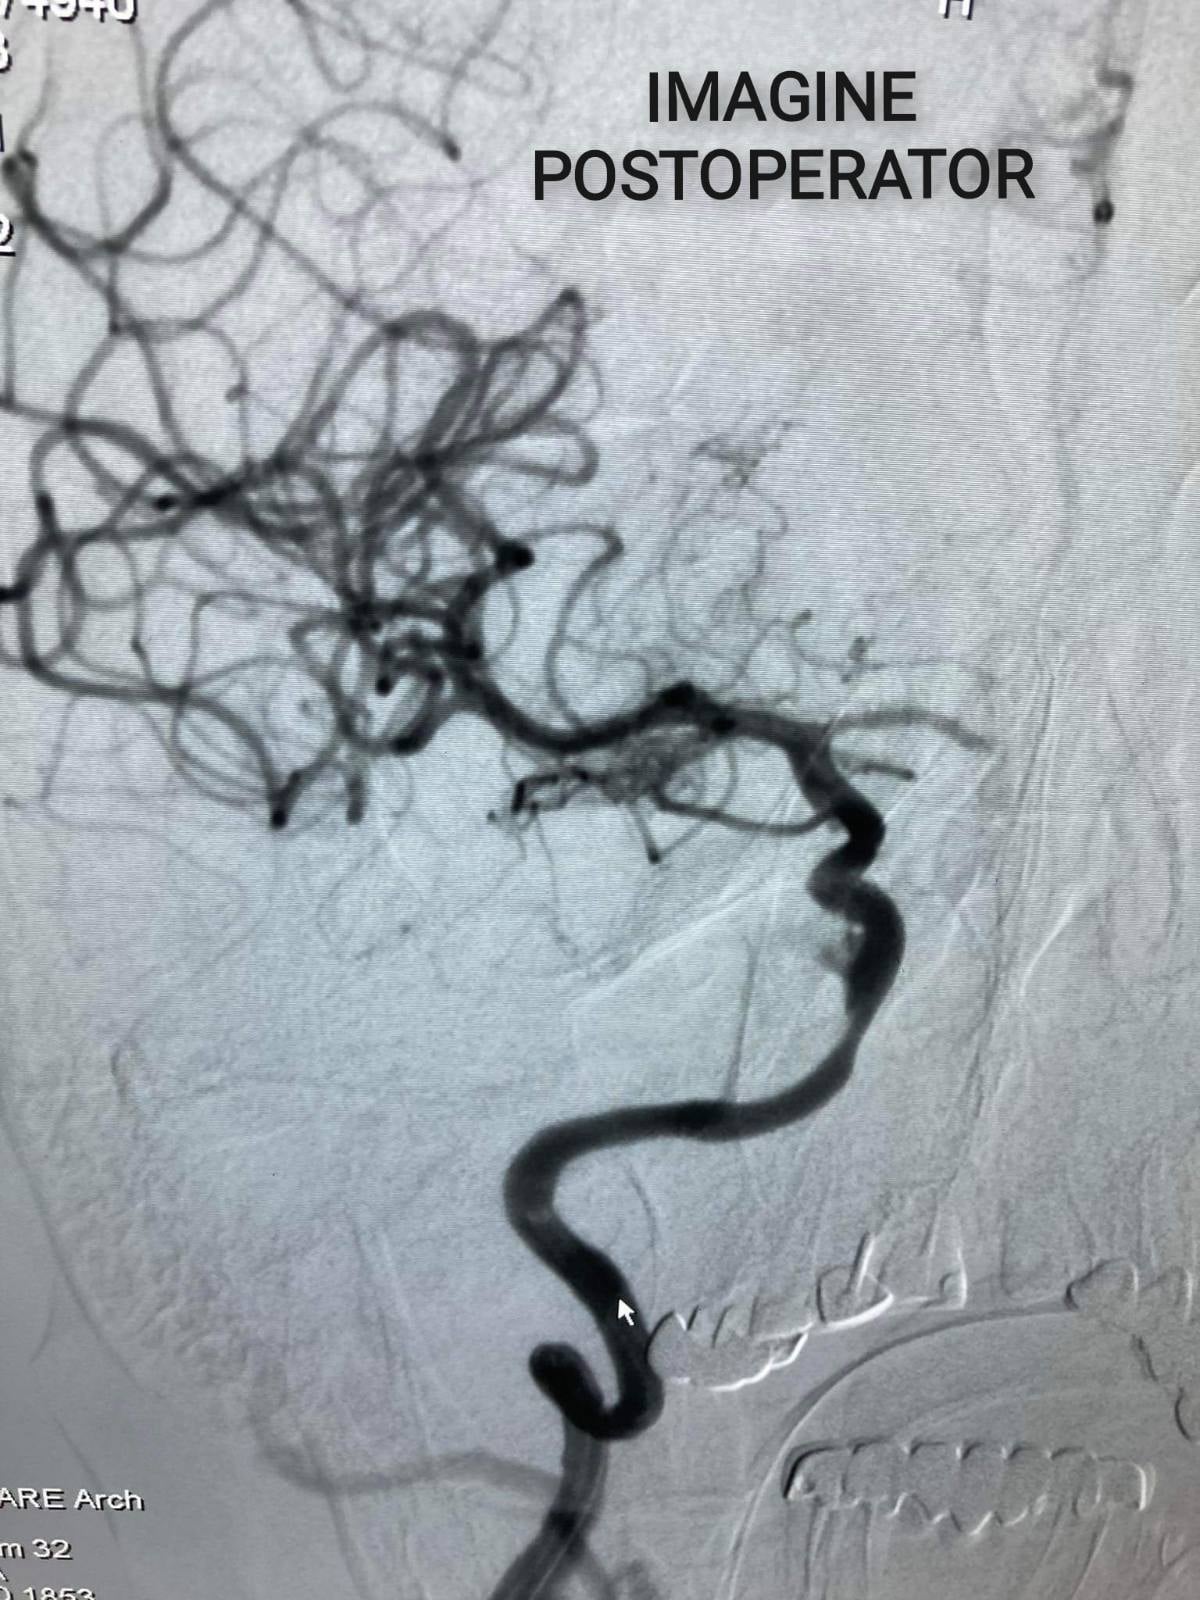

”Pacienta a fost operată în cadrul Cabinetului de cardiologie intervențională. Acesteia i s-a implantat dispozitivul de deviere de flux, prin excluderea anevrismului. Femeia a fost externată în stare satisfăcătoare a doua zi după intervenție. Menționez că, ictusul hemoragic provocat de anevrismele cerebrale complicate cu hemoragie este una din cauzele majore de dizabilitate și deces, iar metoda descrisă soluționează problema anevrismelor cerebrale minimal invaziv fără necesitatea unei intervenții majore pe creier”, a explicat chirurgul endovascular, Sorin Barat.

Aceasta a fost a cincea implantare de flow diverter în cadrul instituției. Prima, fiind în premieră, a fost la fel efectuată de către medicii IMSP SCR ”Timofei Moșneaga” în data de 17 iulie, 2020.